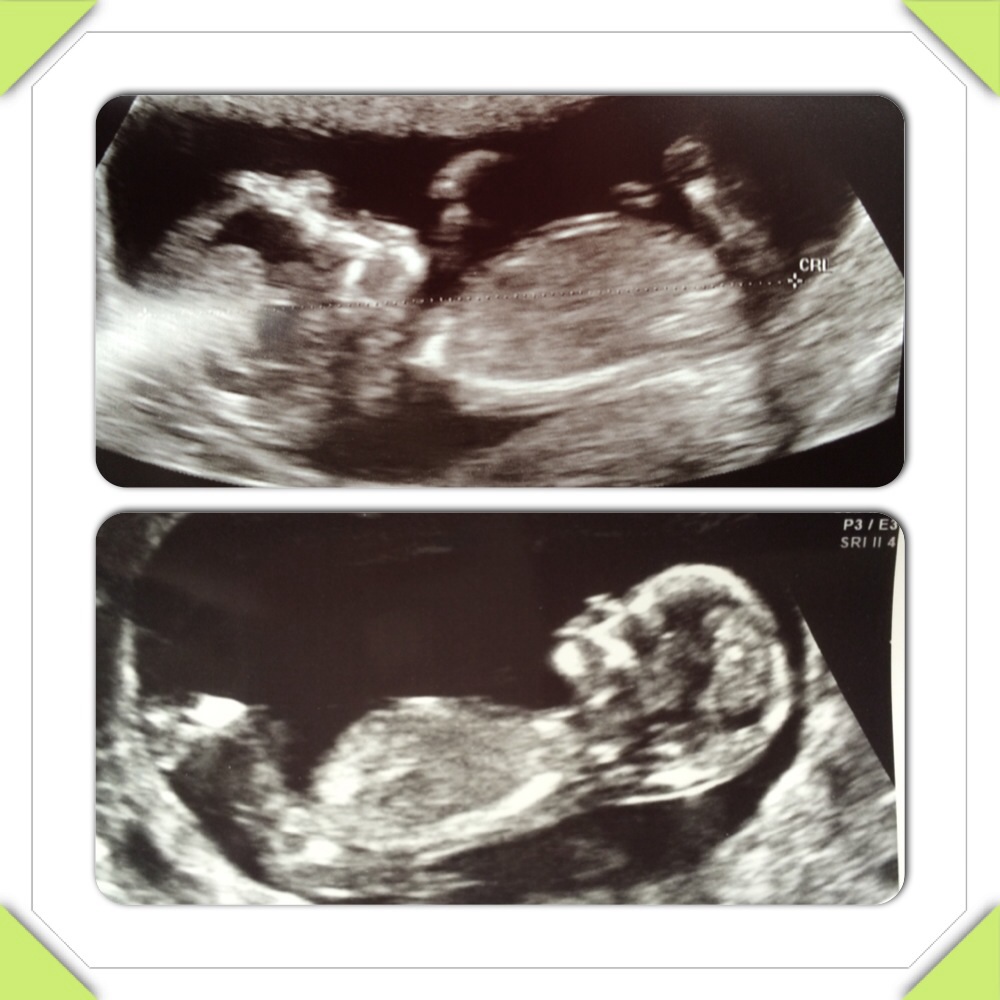

Anyone have any guesses on these cousins??!! Dying to know!! Attachment 18503

Maybe boy

I am not seeing a clear nub